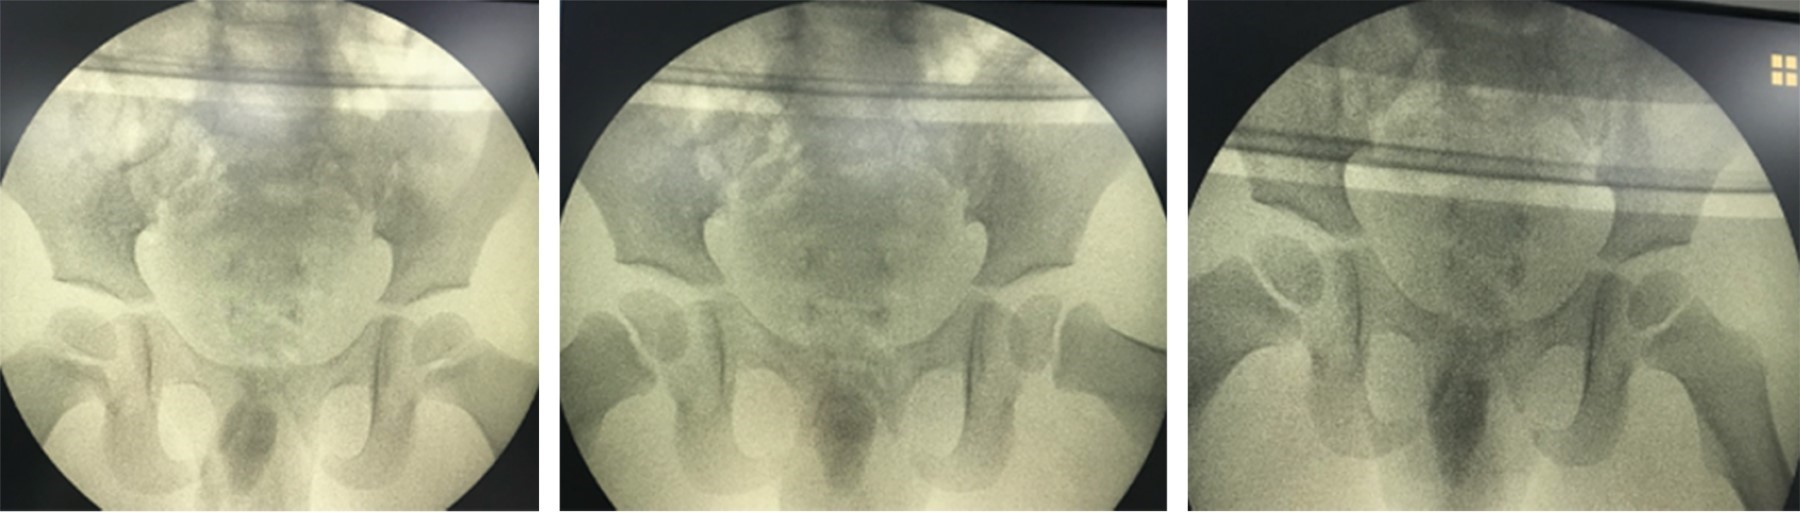

Traumatic anterior hip dislocation in children: a case report

Traumatic anterior dislocation of the hip is uncommon in children, and may result from low energy trauma. Treatment, like all traumatic dislocations, is an emergency. We present the case of a two-year-old boy with traumatic anterior hip dislocation following a fall. Importance: There is little support in the literature for traumatic anterior dislocation of the hip in children due to low energy trauma.

Figure 4

Figure 5

Figure 6